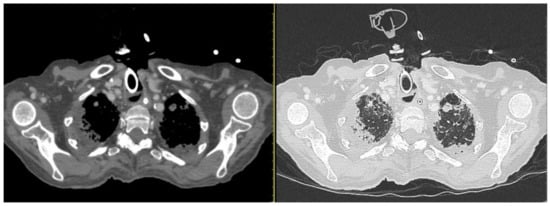

Figure 4.

CT scan on the left. The neck scan revealed the presence of small submucosal bilateral glottic masses, associated with increased cervical lymph node volume, without subglottic and extra laryngeal extensions. (A) Axial section basal CT scan on the left. (B) Axial contrast-enhanced CT on the right. Lung window showing a small scar at the level of the right lower lobe from previous pneumonia reported by the patient; (C) coronal and (D) axial lung window). Due to the worsening conditions, the patient was mechanically ventilated because of acute respiratory failure. Despite the therapy and mechanical ventilation, the pulmonary functions deteriorated progressively, resulting in the patient’s death. The patient was not diabetic, hypertensive, or cardiopathic and was not a smoker. By anamnestic clinical history, we discovered that two years before this event (October 2019), the subject presented mild hoarseness of voice. At the time, an endoscopic laryngeal examination revealed bilateral mobile vocal folds without apparent abnormalities. For further confirmation, the subject underwent a laryngeal exam under general anesthesia, which showed the absence of any macroscopic lesion, and the histopathological results of the biopsies were negative. The physicians scheduled a follow-up after three months, but unfortunately, the lockdown caused by the COVID-19 pandemic and the fear of viral infection prevented her to attend the recommended follow-up visits. The patient was COVID-19-negative throughout the whole illness (Table 1). We performed a literature analysis by searching the PubMed database for ‘laryngeal adenoid cystic carcinoma’. We did not limit the search to article types because of the rarity of the disease and the little number of papers about it. We choose only papers published in English within the past five years. The articles in the database whose full text could not be found were also excluded. The title and abstracts of the identified manuscripts were initially screened and selected by all authors independently (IF, AC, PGM, HE, RA, MF, MR, DM, AG, MdV, CB, and AM) based on their relevance to the review topic. The following set of shared chosen inclusion criteria was applied individually to the selected articles in their full-text version: primary laryngeal affection of adenoid cystic carcinoma and therapy consensus of LACC. The literature search yielded 48 papers. Subsequently, 28 studies were excluded because they did not meet the objective of our review, and 20 studies were included and discussed (Figure 5 and Table 2).